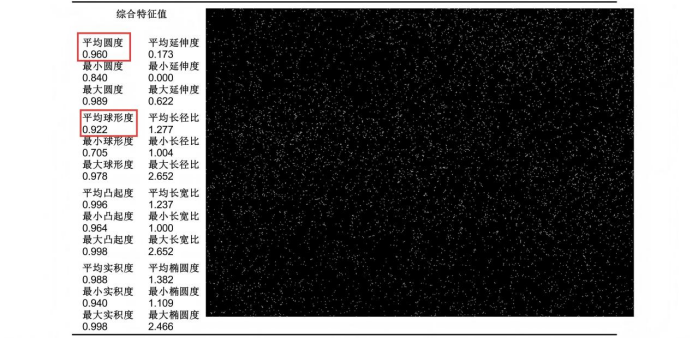

2. 形貌特征:圓整度優異,滿足包衣需求

丸芯的圓整度(圓度、球形度)是包衣工藝的關鍵前提,ZMS850 檢測數據顯示:

1.圓度:平均圓度 0.960(最大值 0.989,最小值 0.840),說明丸芯邊緣光滑,無明顯棱角;

2.球形度:平均球形度 0.922(最大值 0.978,最小值 0.705),接近理想球體(球形度 = 1),可確保包衣液在丸芯表面均勻鋪展;

長徑比:平均 1.277,最大 2.652,且 90% 以上顆粒長徑比<1.3,無明顯細長顆粒,避免包衣過程中丸芯滾動偏移。